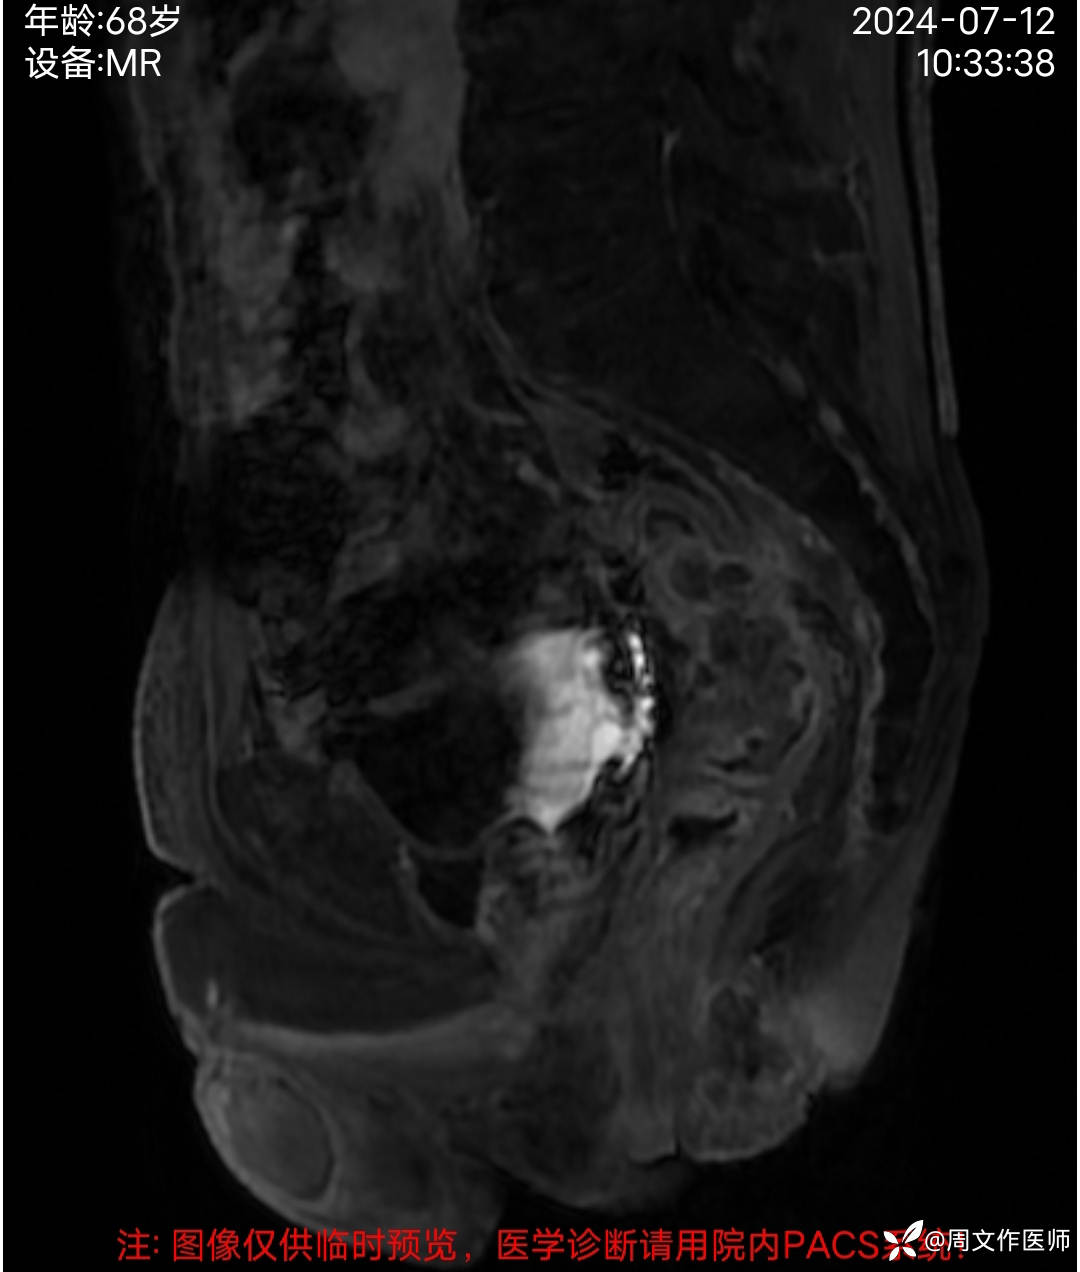

患者男性,68岁,主诉:发现肛门肿物伴出血4年余,加重1月。

现病史:患者诉4年前发现肛门肿物,无疼痛等不适,未引起重视,2年前出现疼痛、出血,脓血溢出至我科住院治疗,完善相关检查确诊直肠癌并发多器官转移至肿瘤科化疗14次,2024年3月因直肠癌肿坏疽穿孔并弥漫性腹膜炎、肠梗阻在外院行 Hartmann手术;病情好转后出院,1月前感肛门肿物逐渐增大,出血及疼痛加重。今日到我院就诊,门诊以"1.肛门肿物;2.便血"收住入院。目前症见:肛门肿物突起,伴疼痛、出血,偶有脓血溢出。病程中患者精神、纳眠稍差,二便正常。体重下降5公斤。

MRI检查